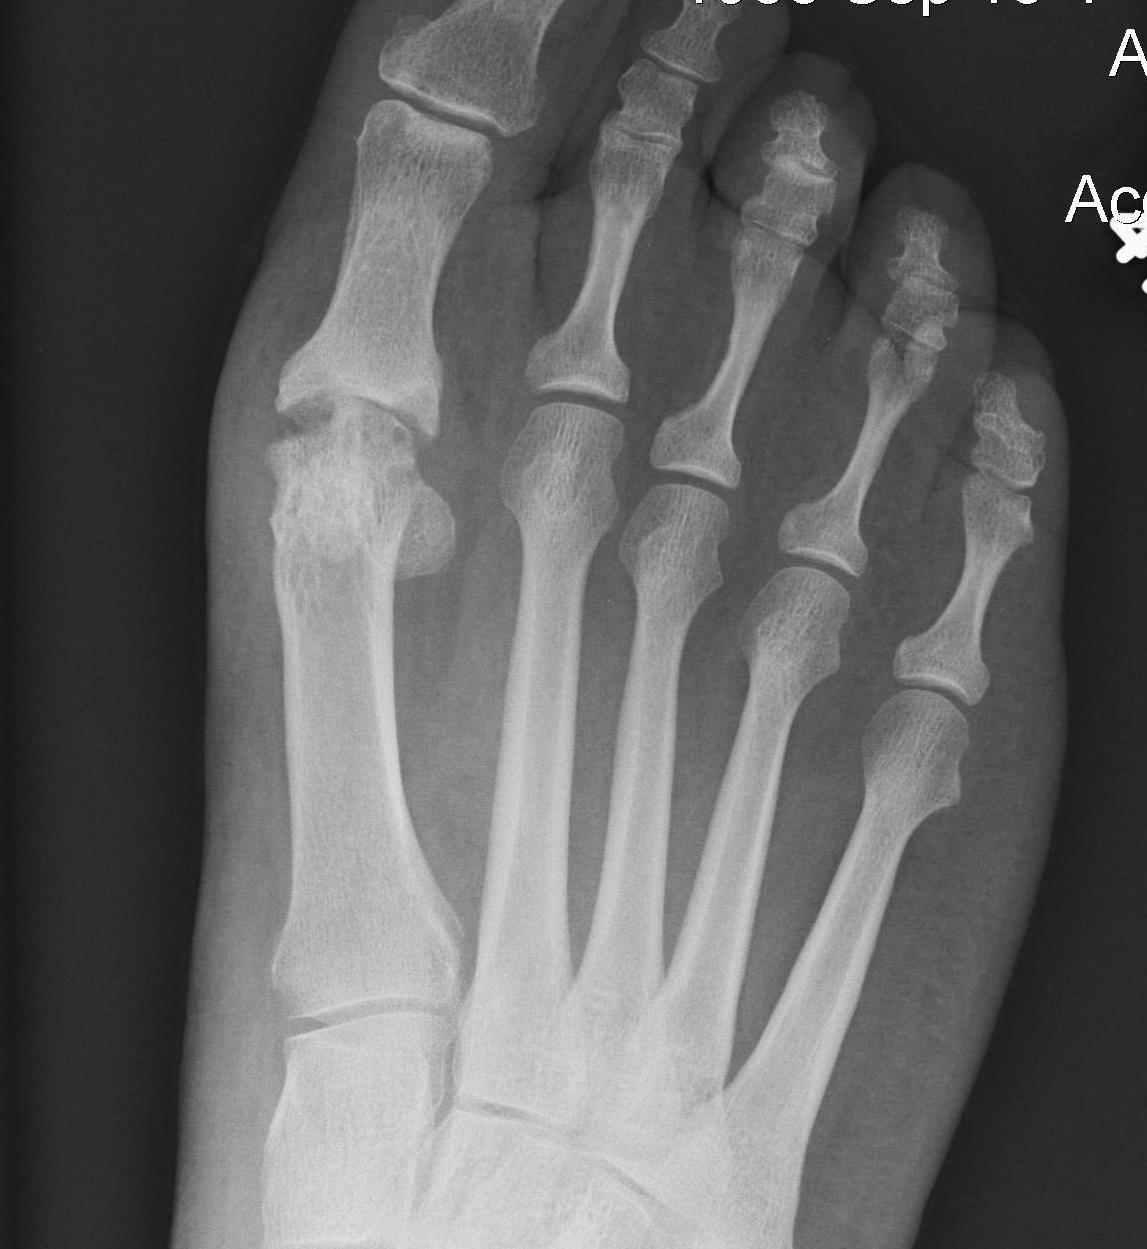

1. Correction of the hallux valgus and intermetarsal angles

2. Creation of a congruent MTP joint

3. Sesamoid realignment

4. Removal of the medial eminence

Chevron osteotomy +/- DSTP

Indications

- incongruent joint

- mild hallux valgus: HVA < 30o / IMA < 15o